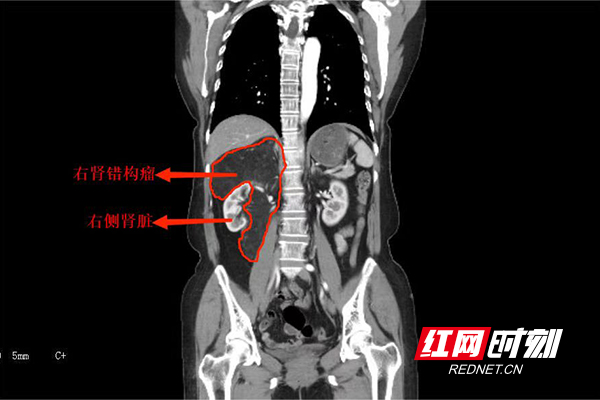

CT结果显示,刘女士右肾被“7”字型肿瘤包裹。

入院后,泌尿外科四病区主任杨科团队为刘女士仔细检查,发现其右肾被“7”字型肿瘤包裹压迫,已经明显移位。这给手术带来挑战,肾脏是血管非常丰富的器官,肾脏血流占心脏排出血量的1/4,如果切除肿瘤同时保留肾脏,手术难度非常大、操作复杂、出血风险高,很有可能出现失血性休克,甚至死亡。经过完善的术前准备,刘女士被送进手术室,术中可见肿瘤紧紧地包裹着肾脏,两者合为一体,周围滋养血管丰富,并且肿瘤深入肾蒂,肾蒂血管在肿瘤中穿行,大量分支为肿瘤供应血运。经过一番努力,手术成功切除肿瘤,并保住了右侧肾脏。